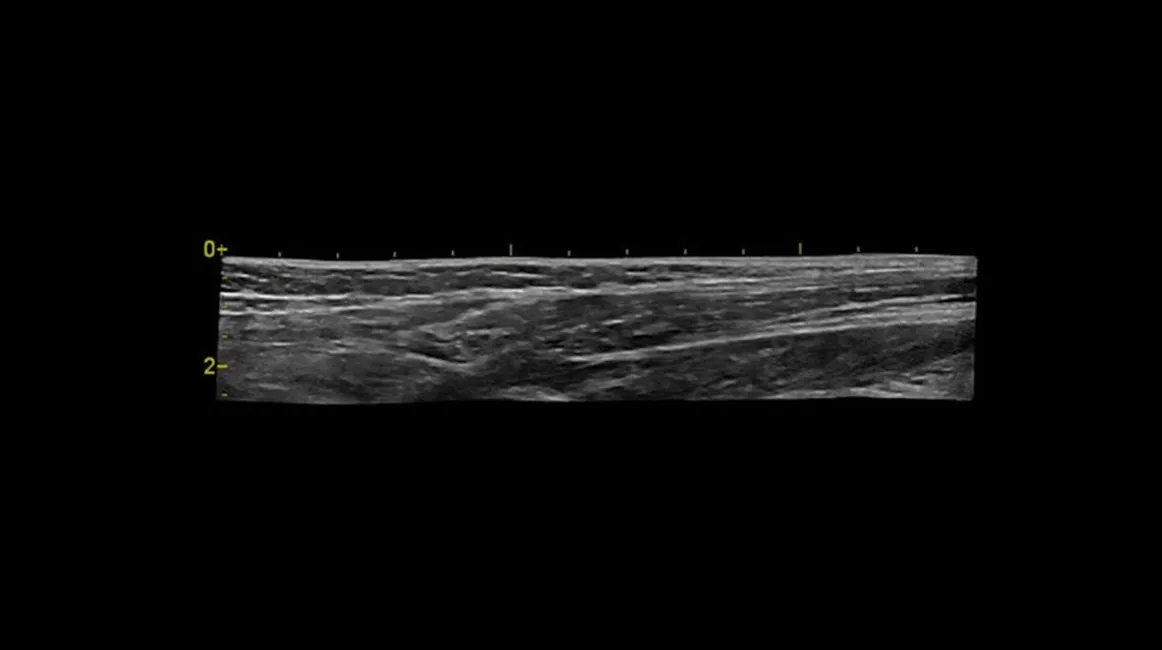

| 9L-RS (линейный) | 3–10 (3,33–10,0) | Линейная широкополосная матрица | — | Периферические сосуды, поверхностные структуры, щитовидная железа, мелкие органы, мышечно-скелетная визуализация |

| L8-18i-RS (линейный высокочастотный) | 4,5–18 | Высокочастотная линейная матричная технология | — | Сосудистые исследования, мелкие органы, поверхностные структуры, мышечно-скелетная и интраоперационная визуализация |

- Сосудистая диагностика: исследования артерий и вен различного калибра, оценка стенозов, тромбозов и нарушений кровотока.